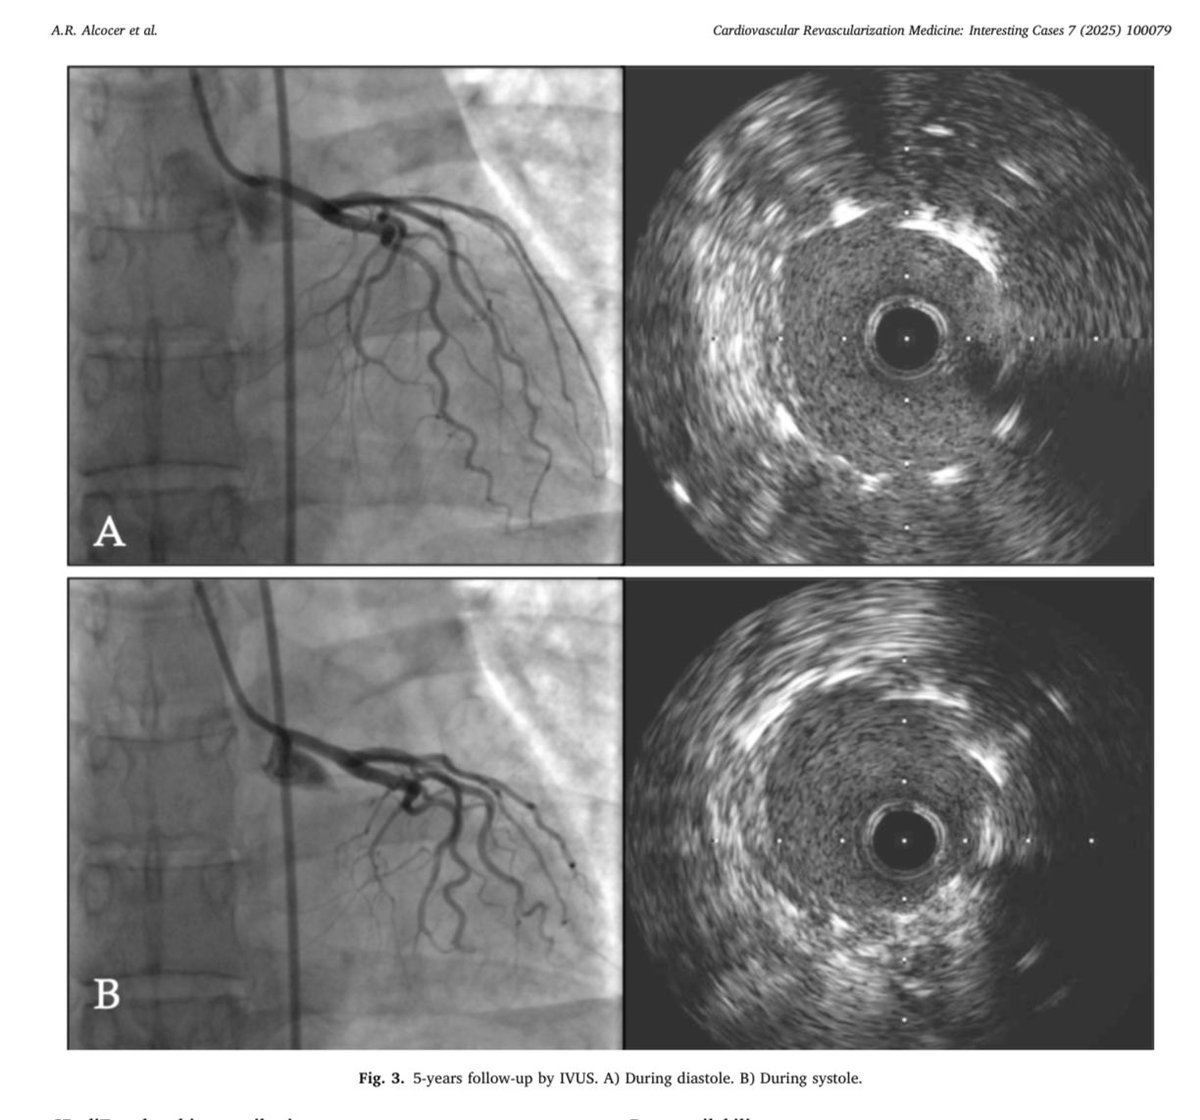

We're excited to share our latest published case report by: @oscarulisesp @drricalde @gpaymd

“Extrinsic left main coronary artery compression in pulmonary hypertension with syncope debut”

kwnsfk27.r.eu-west-1.awstrack.me/L0/https:%2F%2…